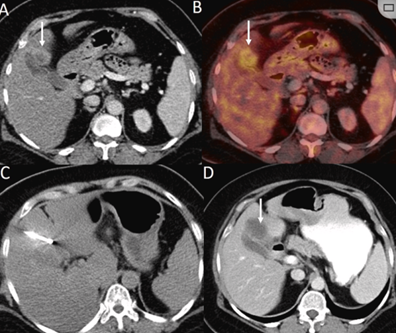

CT引導(dǎo)的冷凍消融

(a) 射頻消融后在病變邊緣顯示殘余增強(qiáng)。(b) 冷凍消融術(shù)中影像顯示冰球完全覆蓋病變。(c) 19個(gè)月后隨訪,沒有發(fā)生局部腫瘤進(jìn)展。完全消融率為97%(66/68);2名患者均接受了額外的冷凍消融,隨后實(shí)現(xiàn)完全消融。平均隨訪期為 12.8 個(gè)月(范圍:3-27 個(gè)月)。所有患者均接受影像復(fù)查(CT 或 MRI)。11個(gè)病灶(16.2%)檢測(cè)到局部腫瘤進(jìn)展,6、12和18個(gè)月時(shí)的累積局部腫瘤進(jìn)展率分別為4%、8.2%和20.5%。8例出現(xiàn)遠(yuǎn)處肝內(nèi)或肝外病變的患者接受經(jīng)動(dòng)脈化療栓塞、經(jīng)動(dòng)脈化療栓塞加射頻消融治療或全身化療。

主要和次要并發(fā)癥發(fā)生率分別為3.5%(2/57)和22.8%(13/57)。并發(fā)癥主要表現(xiàn)為局部皮膚凍傷、中度氣胸、發(fā)熱,僅有少數(shù)患者接受治療,多數(shù)患者自行恢復(fù)。所有患者能耐受圍手術(shù)期疼痛,VAS 評(píng)分范圍在 1-3 分之間(平均 1.65分)。3例患者術(shù)后疼痛加重,VAS評(píng)分達(dá)到4~5分,患者口服止痛藥后逐漸緩解。所有患者術(shù)后1天血常規(guī)、白細(xì)胞計(jì)數(shù)均升高,血小板均有不同程度下降,但變化值均在正常范圍內(nèi)。肝功能1個(gè)月后逐漸恢復(fù)到正常水平。